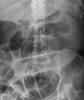

Diverticulosis de colon.